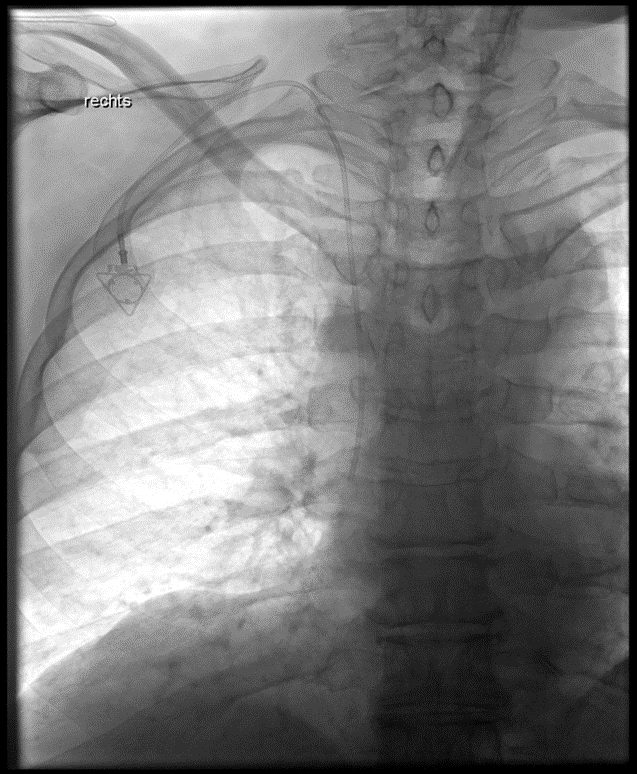

Implantation eines Port-Systems über die rechte innere Drosselvene (V. jugularis interna dextra)

Implantation eines Port-Systems über die rechte innere Drosselvene (V. jugularis interna dextra)

(Bild 1 von 4)